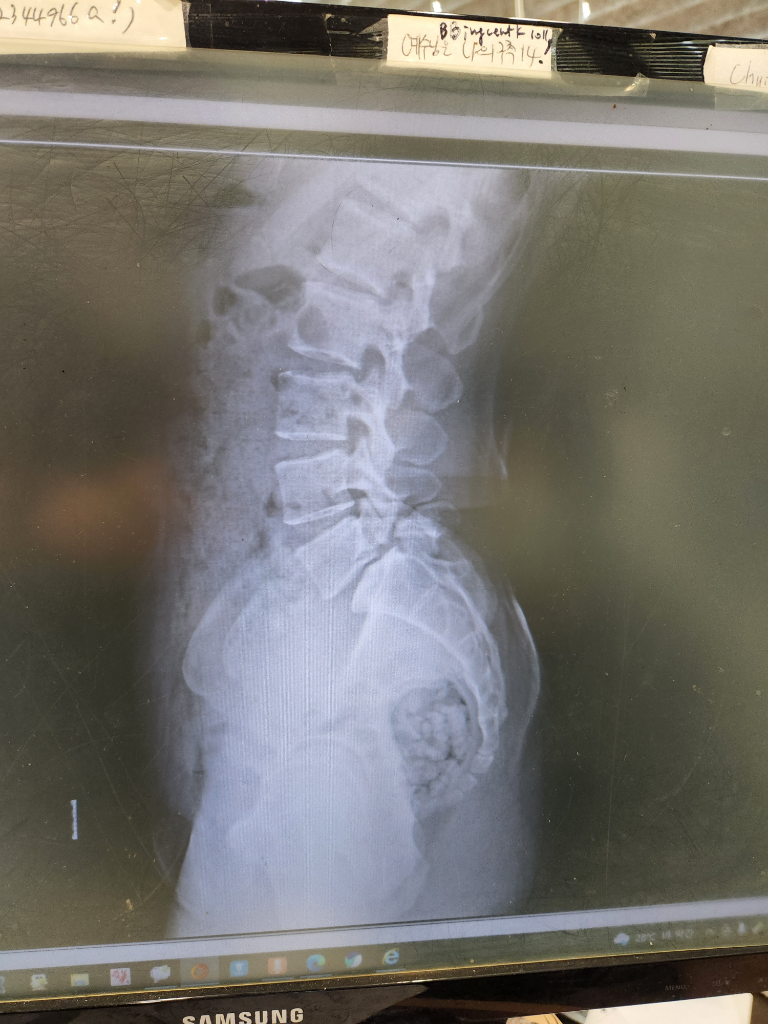

척추분리증으로 다리가 발끝까지 계속 저린데 운동을 해도 될까요?

얼마전 다리가 저리고 엉덩이가 저려서 병원갔더니 척추분리증 진단을 받았습니다.

• 1번 째 사진